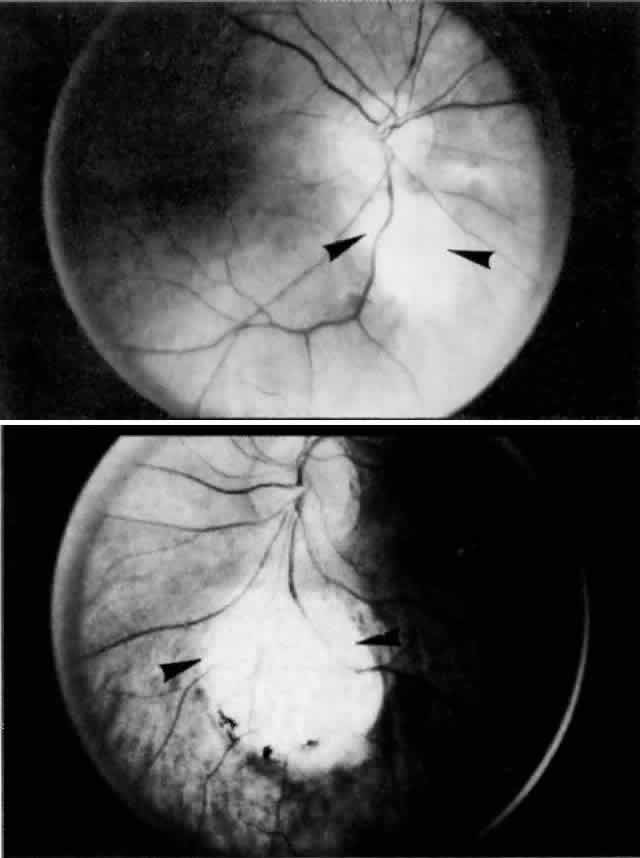

Fig. 7. Asymmetric colobomas (arrowheads) of posterior pole in right (above) and left (below) eyes of same patient. Failure of closure of embryonic fissure results in typical defects in retina and uvea inferonasal to the optic disc.

The funduscopic appearance of ischemic lesions in the choroid has been recognized since the early 19th century. In 1904, Elschnig67 described areas of circumscribed secondary RPE loss (Elschnig's spots), which are now recognized to be signs of ischemic infarcts arising from acute occlusion of the choriocapillaris or precapillary choroidal arterioles (Figs. 32, 33, and 34). Multifocal acute ischemic choroidopathy results from acute ischemic lesions of small choroidal arterioles, whereas geographic choroidopathy is due to an occlusion of larger choroidal arterioles or small arteries.47Triangular or wedge-shaped choroidal lesions appear to be three-sided, the apex pointing posteriorly and the base anteriorly. They are believed to represent evidence of occlusion of larger choroidal vessels. Occlusion of the long or short posterior ciliary arteries or their branches results in triangular defects. Triangular defects caused by obstruction of the short posterior ciliary arteries are more numerous, more irregular, and usually smaller. If the triangles become confluent, they may produce hemiatrophy of a quadrant.47,68

Fig. 32. Area of peripheral choroidal ischemia in gross specimen.

Fig. 33. Photomicrograph of area corresponding to that in Figure 31 shows ischemic atrophy of outer retina and retinal pigment epithelium. (H & E, × 25)

Fig. 34. Flat preparation showing focal atrophy of choriocapillaris in eye with cobblestone degeneration. (AFIP Neg 75-5513; PAS, × 42)

Foulds and co-workers70 presented cases of cranial arteritis documented clinically or clinicopathologically, in which wedge-shaped (triangular) areas of acute retinal edema were associated with visual loss. Recovery of vision occurred with the resolution of the retinal edema and the appearance of pigment clumping in a triangular distribution. The clinical features of these cases were consistent with obstruction of a major branch of one of the short posterior ciliary arteries. Some of their cases of choroidal ischemia showed evidence of choroidal and optic nerve changes. Adjunct studies (hue discrimination and electro-oculography) supported the etiology of outer retinal injury instead of a primary optic neuropathy. Because the optic nerve head is supplied by the short posterior ciliary arteries, as is the choroid, the findings of disturbances in the choroidal flow and optic nerve ischemia could be explained readily.